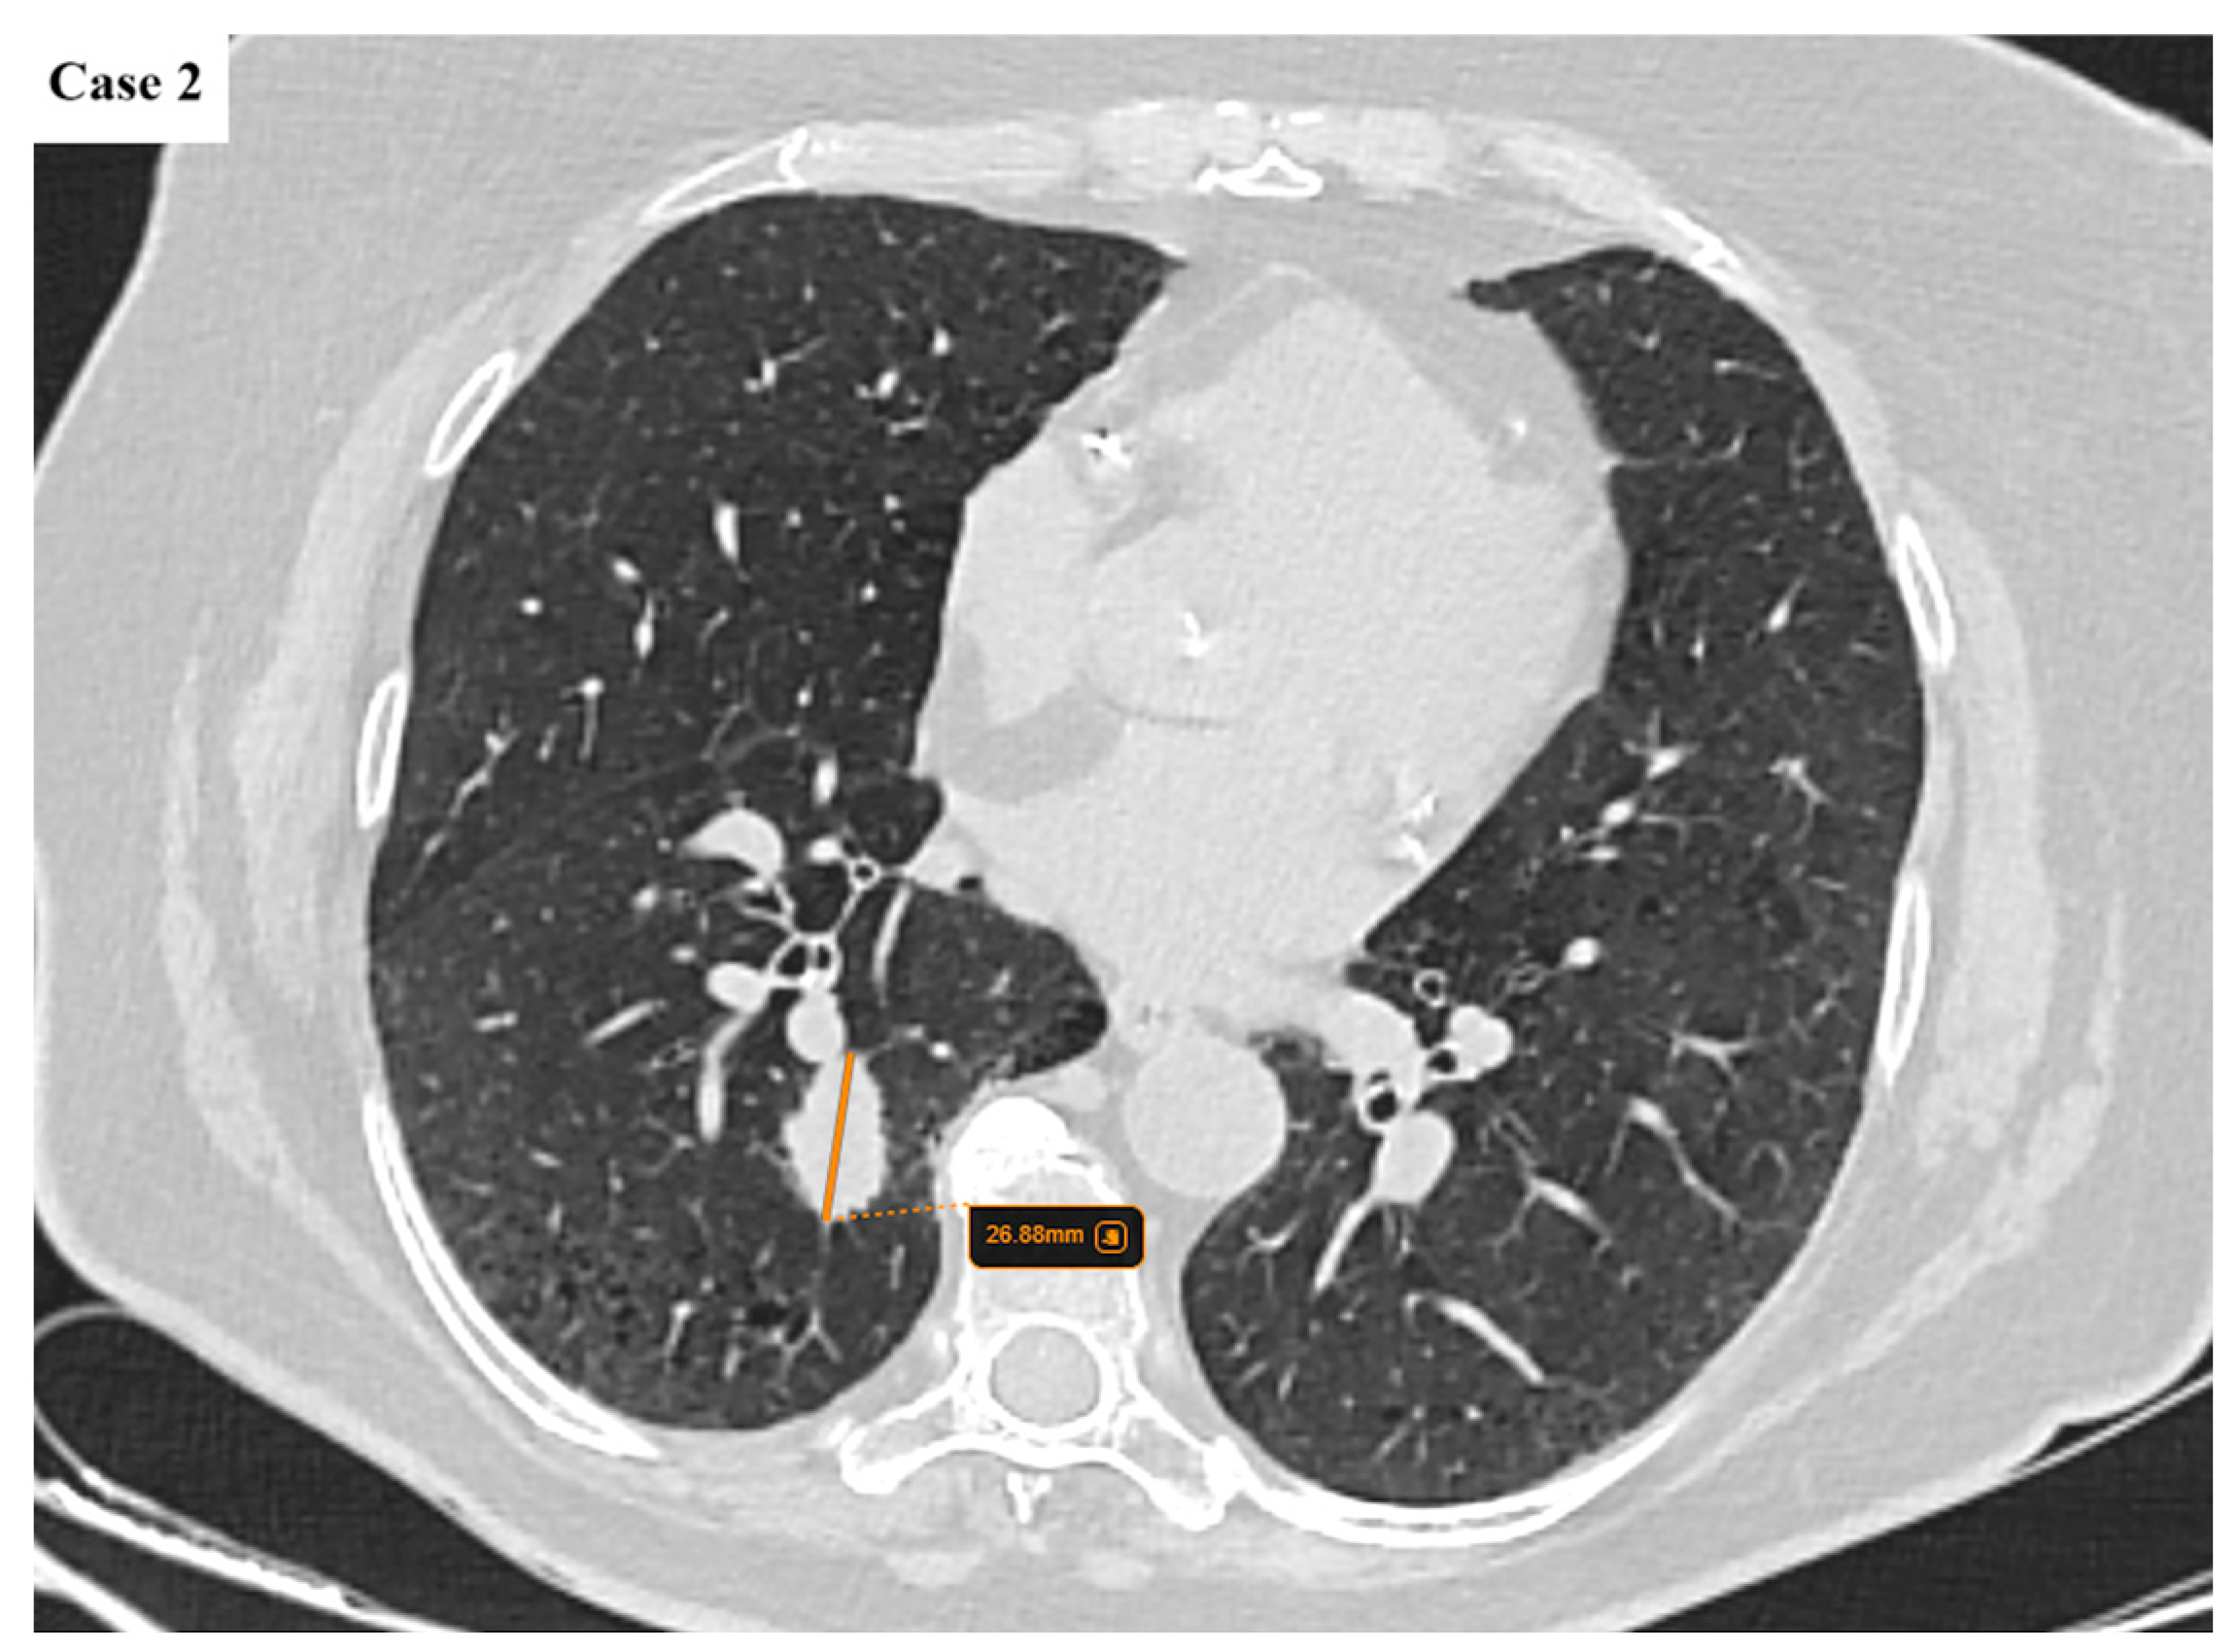

- Argentieri, G.; Valsecchi, C.; Petrella, F.; Jungblut, L.; Frauenfelder, T.; Del Grande, F.; Rizzo, S. Implementation of the 9th TNM for Lung Cancer: Practical Insights for Radiologists. Eur. Radiol. 2025, 35, 4395–4402. [Google Scholar] [CrossRef] [PubMed]

- Erasmus, L.T.; Strange, C.D.; Ahuja, J.; Agrawal, R.; Shroff, G.S.; Marom, E.M.; Truong, M.T. Imaging of Lung Cancer Staging: TNM 9 Updates. Semin. Ultrasound CT MRI 2024, 45, 410–419. [Google Scholar] [CrossRef]